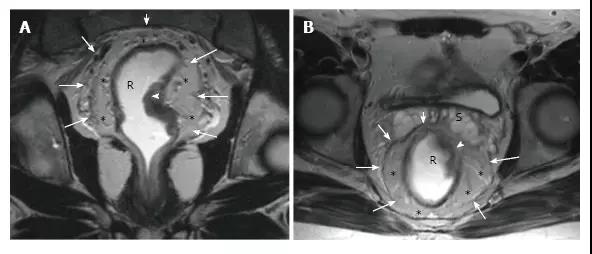

图 6. 直肠系膜和直肠系膜筋膜共振成像解剖学。在 T2 加权(A. 轴位和 B. 冠状位)磁共振图像上,直肠系膜筋膜(箭头)被看作是一个薄的低密度层,包围男性直肠癌患者的直肠系膜脂肪组织(*)和直肠。